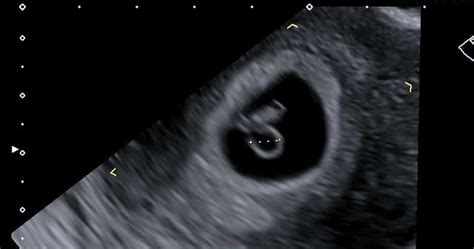

An ultrasound is performed at this stage of pregnancy to confirm your due date, confirm if you are having singles, twins or more and to visualise your baby's heart beating.

I'm having such a hard time getting into the local ob's so we are paying private at a 4d center to get a 2d dating scan. Dating scans are offered at some point between 8 and 14 weeks, with most of them happening between 11 and 14 weeks. You will need to get a referral from your doctor or midwife for a dating scan. An ultrasound is performed at this stage of pregnancy to confirm your due date, confirm if you are having singles, twins or more and to visualise your baby's heart beating. The mother's reproductive health is checked. A 7 week scan is sometimes called a dating scan, because it's an accurate way of assessing a baby's age and growth. We told quite a few after the scan as we had the pic and all was going well. Gestational age is determined using the baby's size and offer an accurate estimation of when the baby was conceived. There are many moms who have done the same and have had accurate results. This is just incase there's a slight discrepancy with your dates. Women who have a history of complications when it comes to pregnancy can go for it earlier. You'll only have a scan before 10 weeks in certain situations. 8 weeks + 0 days and 9 weeks + 3 days.

We will book you in from 2 weeks after your first positive pregnancy test. The dating scan is an ultrasound that can be done from seven weeks of pregnancy but they usually happen a little later. This gives the pregnancy a gestation of approximately This is just incase there's a slight discrepancy with your dates. Ultrasound is almost foolproof at diagnosing twins. This is called the dating scan. The gestational age of the baby can be determined by the dating scan. This ensures you're at least 6 weeks.